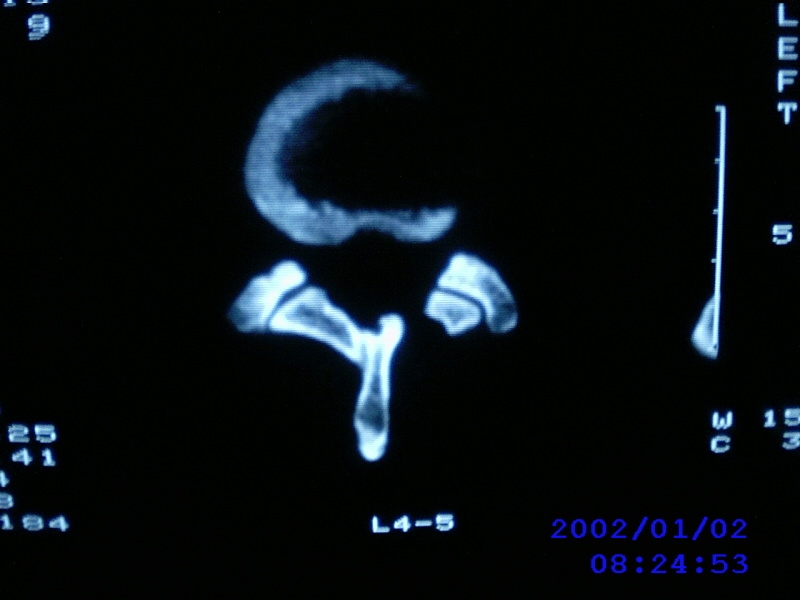

患者,男性,40岁,腰痛伴左下肢疼痛、麻木6年。5年前做过腰椎间盘手术,具体是哪个位置病人记不清了。

我拍的是l4-5、l5-s1

1)l4/5及l5/s1左侧椎板术后改变。2)l5/s1椎间盘突出,l5椎体下缘许莫氏结节。3)l4/5椎间盘膨出并突出。4)l3/4椎间盘膨出。

1)l4/5及l5/s1左侧椎板术后改变。2)l5/s1椎间盘突出,l5椎体下缘许莫氏结节。3)l4/5椎间盘膨出并突出。

1)l4/5及l5/s1左侧椎板术后改变。2)l5/s1椎间盘突出,l5椎体下缘许莫氏结节。3)l4/5椎间盘膨出并突出。4)l3/4椎间盘膨出。支持!